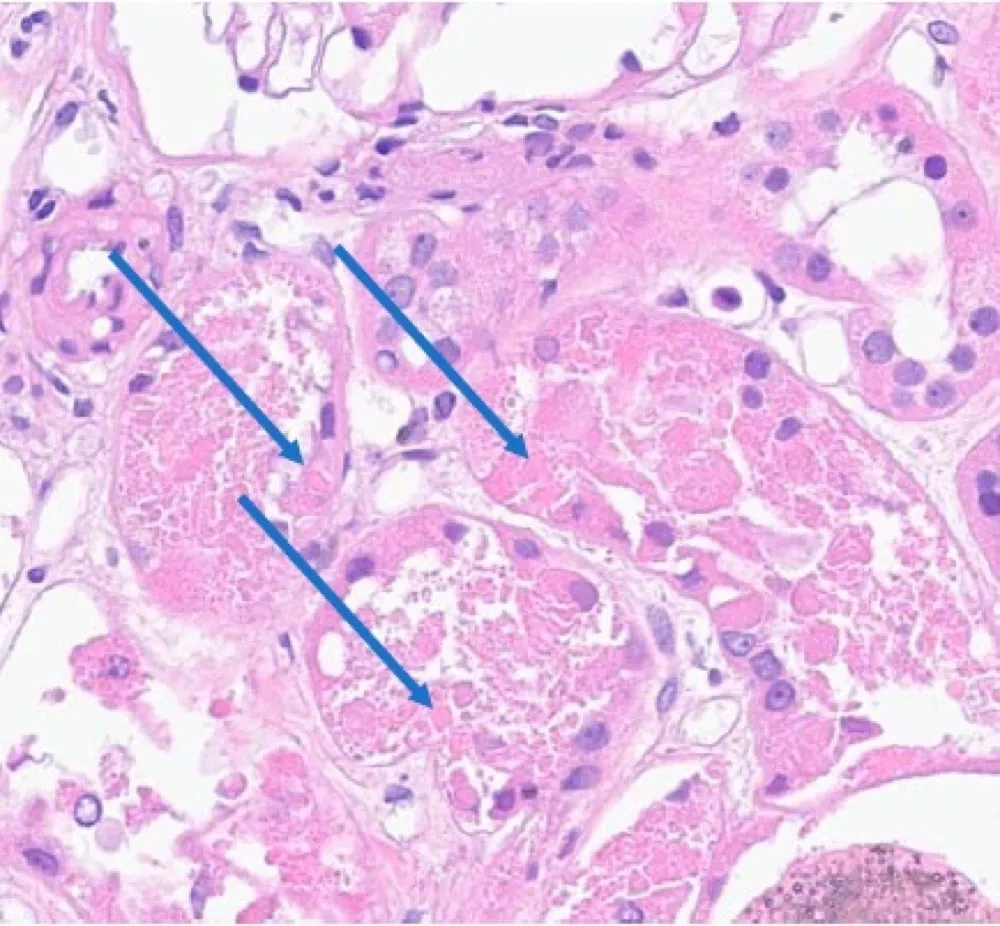

Microcistos renais e lítio: existe relação? O uso crônico de lítio pode impactar os rins, mas qual o papel dele na formação de microcistos renais? Entenda o que a literatura recente revela.

Valkercyo Feitosa

12 meses atrás